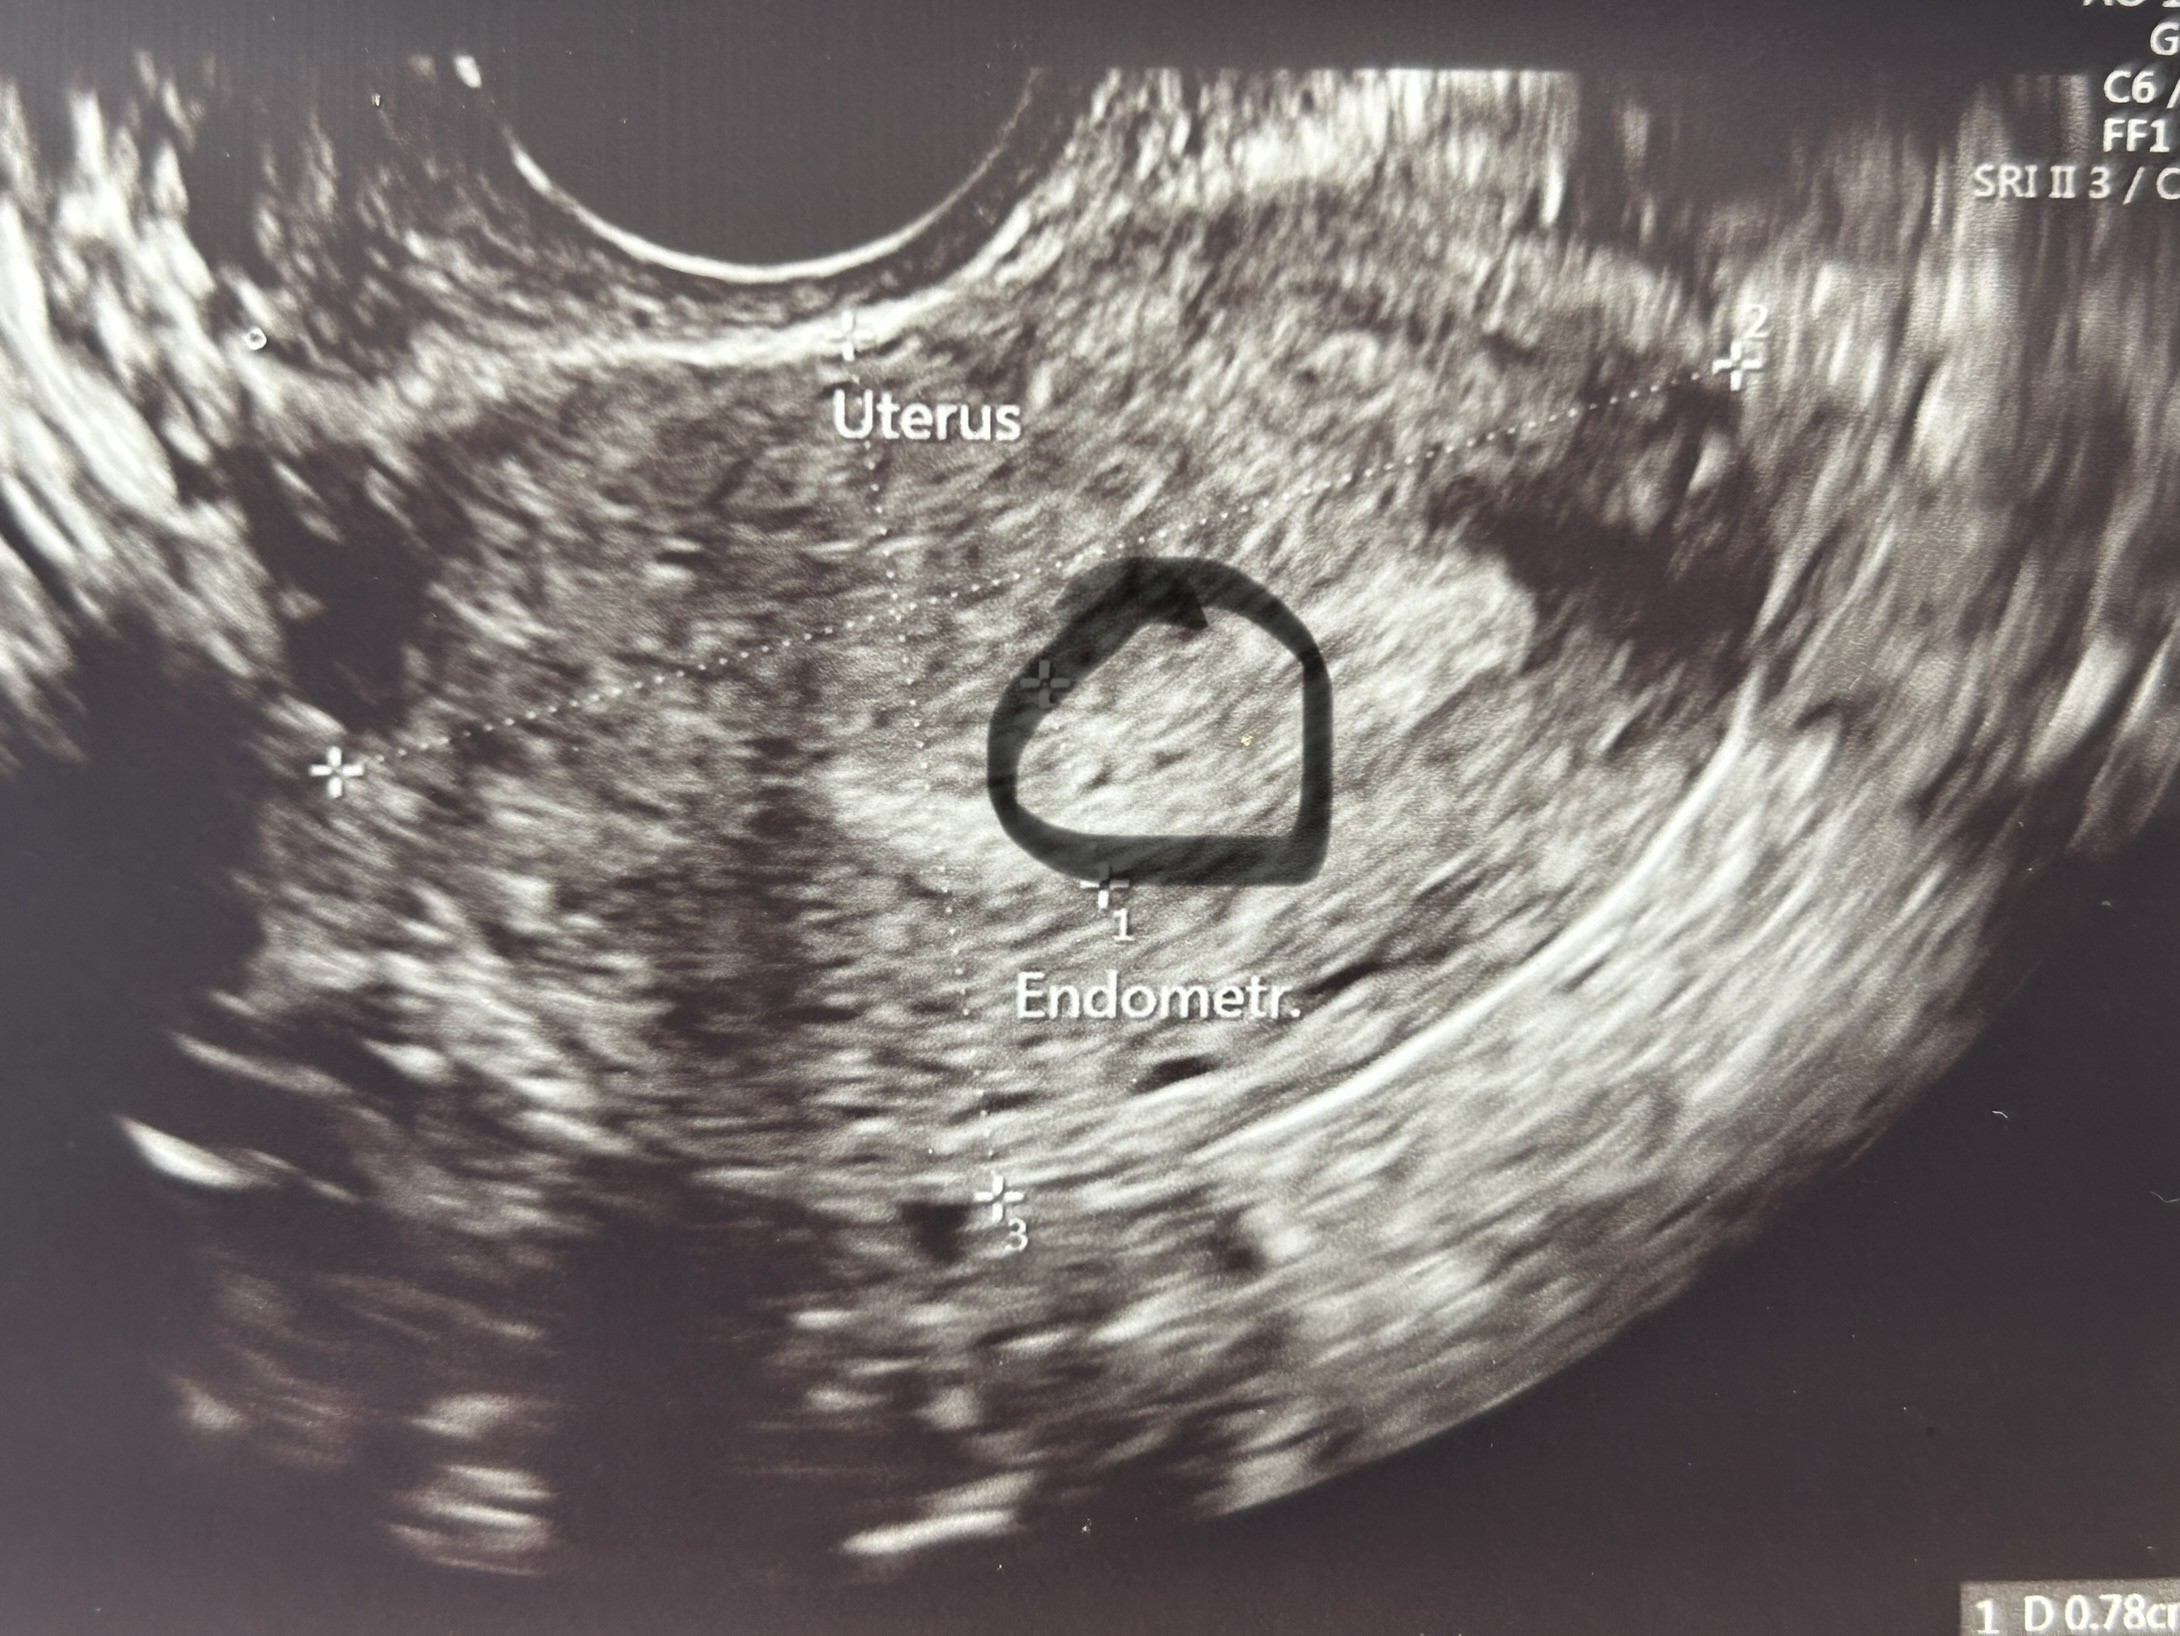

Cześć, u mnie dziwna sytuacja bo testy z moczu i krwi wychodzą negatywne

Beta hcg <0.100

Ostatnia miesiączka 22.08

Niebezpieczne współżycie 9.09

Owulacja prawdopodobniej była 13.09 trochę opóźniona

Od 18.09 do dziś okropne bóle podbrzusza w okolicy lewego jajnika, pieczenie w brzuchu, ból po środku brzucha, okropna zgaga , brak chęci do jedzenia, zaparcia, dziwne sny

Niby ginekolog nie widzi ciąży a po czasie spoglądam na usg a tam taka fasolka

Może to świadczyć o ciąży?

Gdzie ty masz fasolkę? 🤣 Ty chyba nie wiesz jak wygląda pęcherzyk ciążowy 🙈